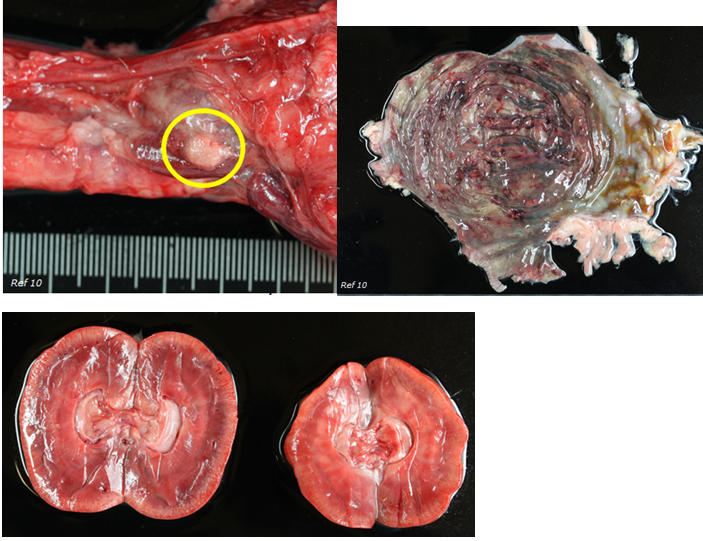

Case B

Cat

Domestic short hair

12 years 9 months

Female neutered

Abnormal left kidney. Surgical resection was attempted but then aborted. Presenting with anorexia and oedema on caudal part of body. Euthanasia.

What is your diagnosis?

Diagnosis:

Renal carcinoma with severe hydronephrosis and medullar atrophy